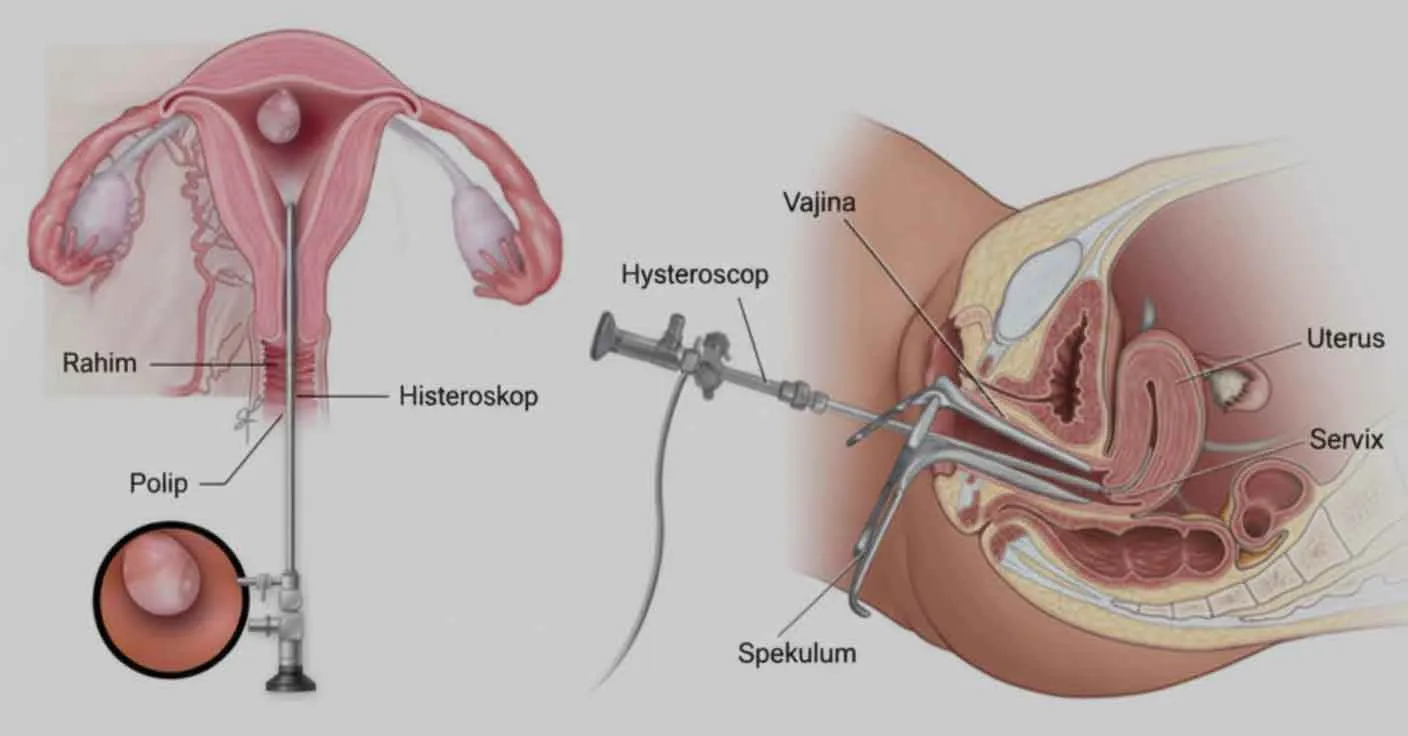

Tüp bebek öncesi histeroskopi ne zaman gerekir? İlk IVF denemesi, tekrarlayan implantasyon başarısızlığı, polip, miyom, yapışıklık, SIS ve HSG kararlarını kanıta dayalı özetleyen rehber.

Histeroskopi nedir, ne zaman yapılır? Polip, submüköz miyom, septum, rahim içi yapışıklık, anormal kanama ve IVF öncesi rahim içi değerlendirme için tanı-tedavi rehberi.

Asherman sendromu için modern tanı (histeroskopi), AFS-ESGE-March sınıflandırması, histeroskopik adheziolizis sonrası gebelik oranları, rekürrens önleme stratejileri (balon, estrojen, hyaluronik asit) ve plasenta akreta dahil obstetrik risk yönetimi.

Miyom ameliyatı ne zaman gerekir? Submüköz, intramural ve subseröz miyomlarda ameliyat kararı, gebelik planı, IVF, histeroskopi ve laparoskopi seçenekleri.